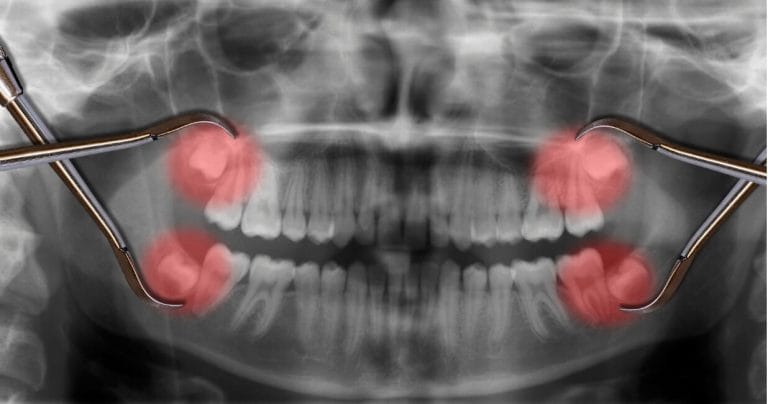

Ova operacija zuba podrazumeva hirurško vađenje umnjaka, a obavlja se zbog:

Iz različitih razloga, npr. u slučaju zaostalog zubnog korena ili impaktiranih zuba, ponekad kod vađenja zuba oralna hirurgija mora da priskoči u pomoć. Prilikom oporavka treba paziti na zarastanje rane, što uz pridržavanje naših saveta ne bi trebalo da bude problematično.